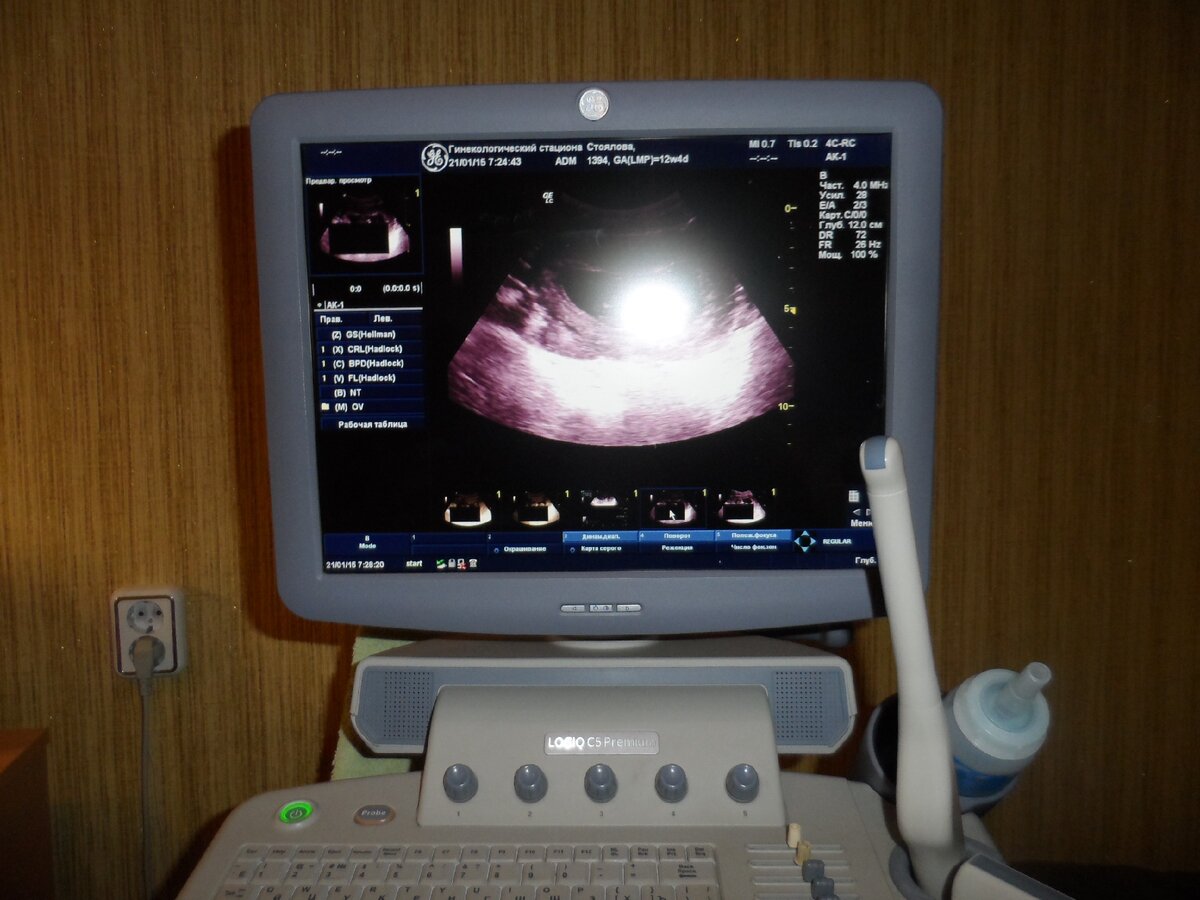

Вот таким образом, на экране, врач увидит дефекты развития